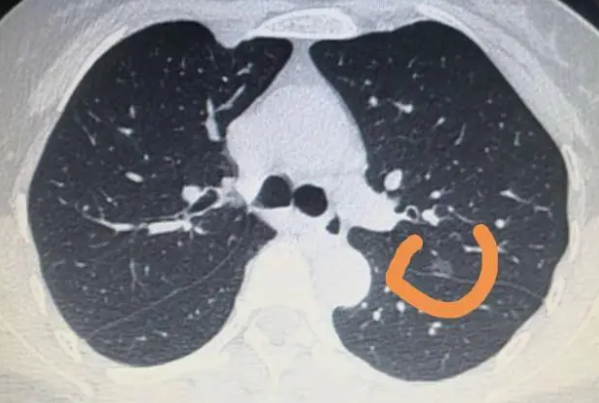

肺部小结节是胸外科的常见病和疑难病,其诊断和治疗一直是临床疑难病症和热议的话题,其病因复杂,临床表现不特异,诊断有难有易。易误诊和漏诊。周围型肺癌直径≤2cm者称为小肺癌,直径≤1cm者称为微小肺癌。小肺癌不完全是早期肺癌,尤其是腺癌和小细胞未分化癌,根据文献资料,约20%的小肺癌患者有淋巴结微转移。因此,部分患者会错过手术的最佳时机。肺部小结节生理解剖所见较多,可合并成块状或单个圆形肺结节,直径1~2cm,后期可空洞或合并感染。